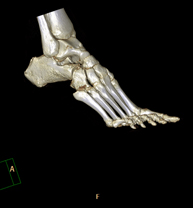

Exploració radiològica que mitjançant un sistema de raigs X i detectors que giren al voltant del pacient i que reconstrueixen les imatges per ordinador (TC Multidetector), permet l'estudi detallat dels ossos, els músculs i les articulacions del genoll. - TC de turmell-peu

Exploració radiològica que mitjançant un sistema de raigs X i detectors que giren al voltant del pacient i que reconstrueixen les imatges per ordinador (TC Multidetector), permet l'estudi detallat dels ossos, els músculs i les articulacions del turmell i el peu. - TC d'estudi rotacional EEII (Bàscula rotuliana, distància TA-GT)